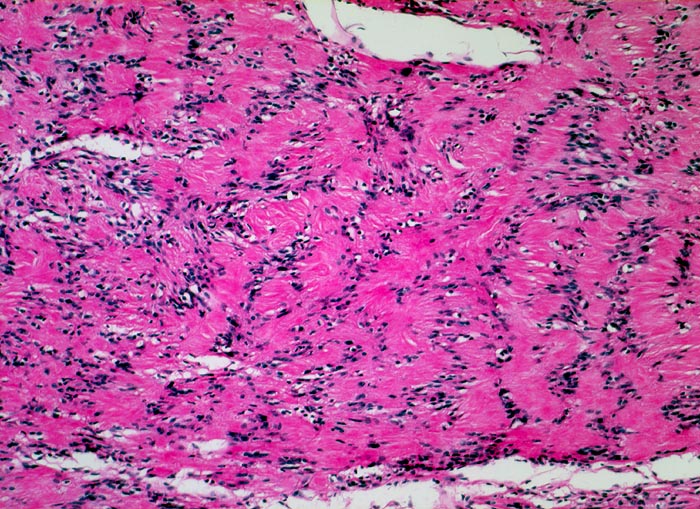

Die histomorphologischen Befunde sind sehr variabel. Am häufigsten bestehen die Tumoren aus Zellzügen mit bipolar orientierten länglichen oder gewellten Kernen und langen Zellfortsätzen. In den sogenannten Antoni A Arealen (> 4295) sind die Zellen in kompakten Bündeln angeordnet, teilweise in Form von Verocay bodies (> 493) (alternierende Anordnung von Kernreihen und Zellfortsätzen). In den Antoni B (> 4296) Arealen bilden die Fortsätze der eher sternförmigen Tumorzellen ein lockeres Geflecht. Einzelne grosse, unregelmässig geformte und hyperchromatische Kerne und flächenhafte Nekrosen, Hyalinisierung oder fokale Verkalkungen sind Ausdruck degenerativer Veränderungen (sogenanntes ancient schwannoma (> 4299)) und dürfen nicht als Zeichen der Malignität fehlinterpretiert werden.

• Biphasischer Tumor mit überwiegend kompakten (Antoni A Muster) und kleinen lockeren, hellen Arealen (Antoni B Muster).

• Antoni A Muster: Parallele Anordnung der Zellkerne und Zellfortsätze (Verocay bodies).